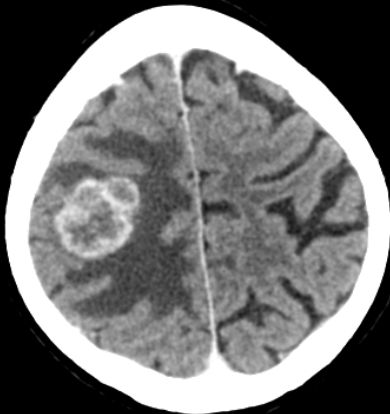

| Hirnmetastasen | Pat. fiel in der Nachsorge wegen einer Apraxie der linken Hand bei erhaltener Kraft und Sensibilität auf. Große Rindenmetastase rechts. Durch das ausgeprägte Ödem wird der intergyrale Liquorspalt rechts vollständig komprimiert. | ||